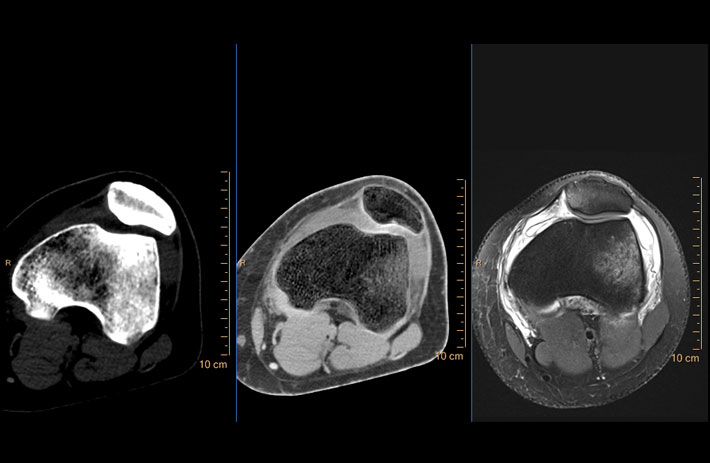

Mit dem Spektral-Detektor-CT werden Spektraldaten automatisch bei jedem Scan erfasst. Die Informationen stehen jederzeit auf der Scankonsole, der CT-Workstation sowie an jedem PACS-Arbeitsplatz zur Verfügung, sodass es nicht notwendig ist, den Patienten erneut zu scannen, bspw. wenn initial zufällige Anomalien festgestellt wurden. Dadurch profitieren Anwender durch eine höhere Diagnosesicherheit und weniger Nachuntersuchungen auf anderen bildgebenden Systemen. Unsere Fallsammlung zeigt, welchen klinischen Mehrwert der Spektral-Detektor-CT in unterschiedlichsten Anwendungsbereichen in der klinischen Routine bringt. Jede Woche gehen neue Fälle live.